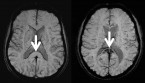

Pero no toda la grasa corporal es la misma. La grasa subcutánea se encuentra justo bajo la piel, y la grasa visceral o intraabdominal se encuentra bajo el tejido muscular en la cavidad abdominal. La genética, la dieta y el ejercicio contribuyen al nivel de grasa visceral que se almacena en el cuerpo. El exceso de grasa visceral se considera especialmente peligroso, porque en estudios previos se le ha asociado con un mayor riesgo de padecer enfermedades cardíacas.![[Img #11256]](upload/img/periodico/img_11256.jpg)

El equipo de la Dra. Miriam Bredella, radióloga en el Hospital General de Massachusetts, y profesora de radiología en la Escuela Médica de la Universidad de Harvard, en Boston, ambas instituciones en Estados Unidos, evaluó a 35 hombres obesos con una edad media de 34 años y un índice de masa corporal (IMC) medio de 36,5. A los hombres se les examinó mediante tomografía computerizada del abdomen y el muslo para evaluar la masa muscular y grasa, así como con tomografía computerizada de muy alta resolución del antebrazo. Estos escaneos, y una técnica especial de análisis (comúnmente empleada en la ingeniería mecánica para determinar la resistencia de materiales para el diseño de puentes o aviones, entre otras cosas) se usaron para evaluar la fortaleza ósea y predecir el riesgo de fracturas.

Los resultados del estudio indican que los hombres que tenían más grasa abdominal visceral y total presentaron valores menores en dos parámetros importantes de fortaleza ósea, en comparación con los hombres que tenían menos grasa visceral y abdominal. No se encontró asociación alguna entre la edad o el IMC total y las propiedades mecánicas del hueso.